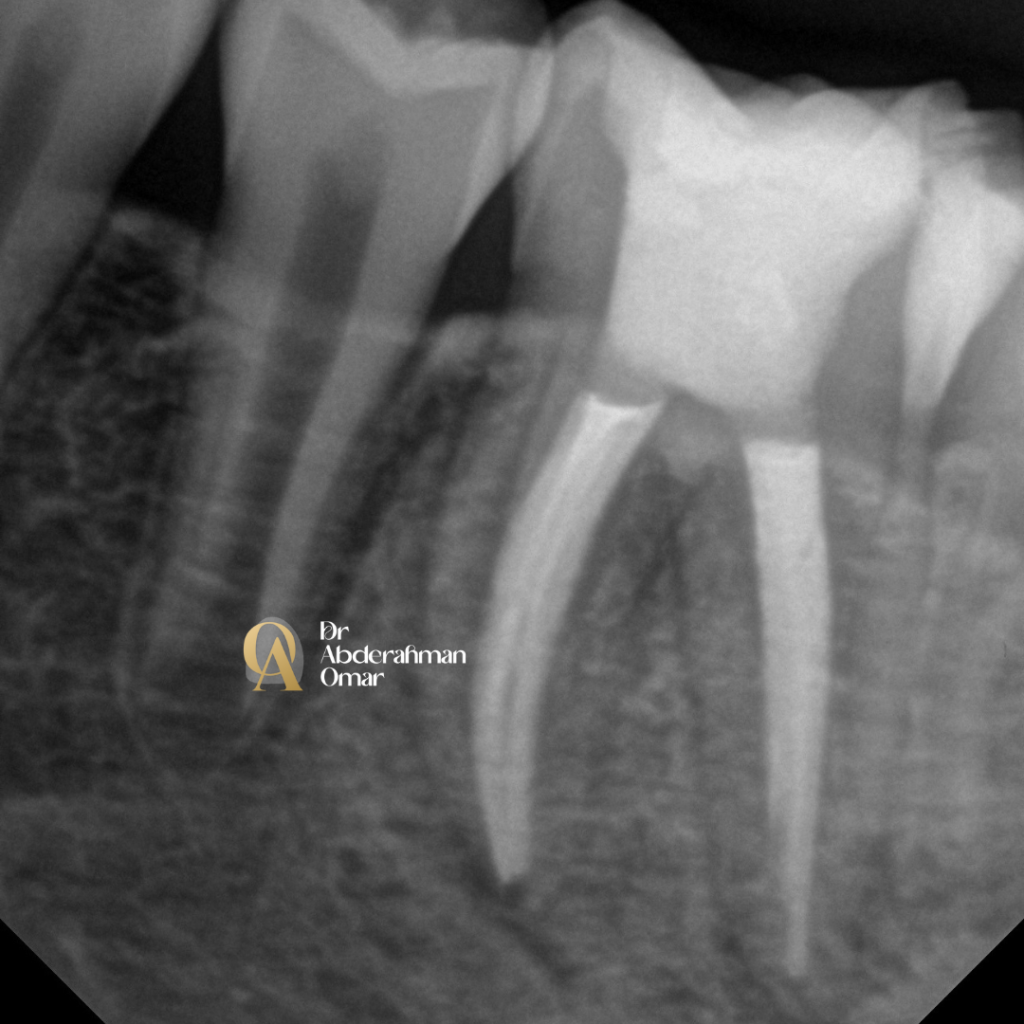

• Working length determination with electronic apex locator and radiographic confirmation

Post-operative radiograph confirmed optimal length, fill density, and canal obturation in all five canals.